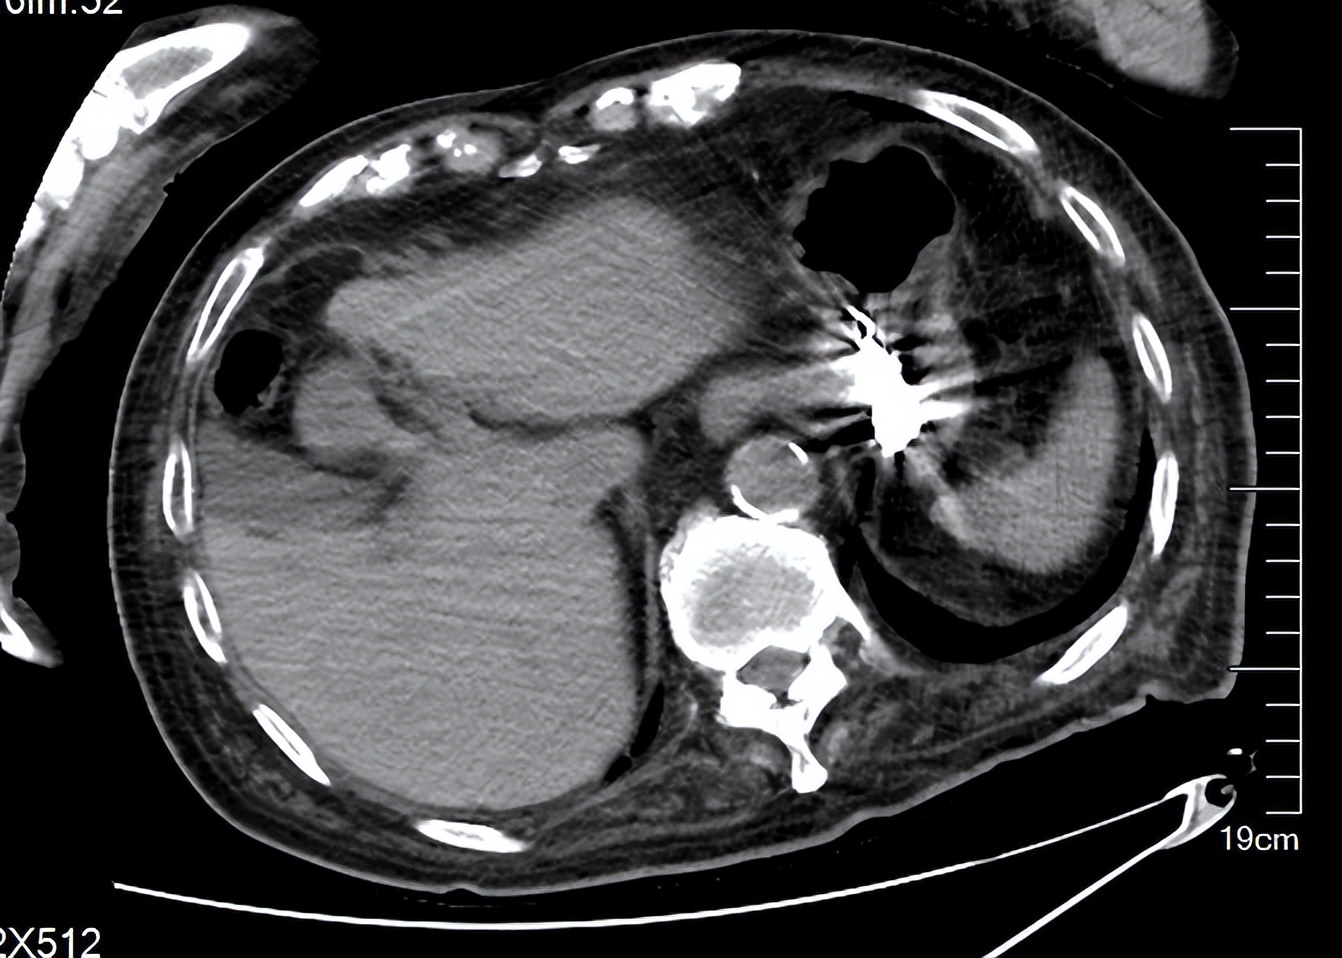

逸夫医院消化内科接诊后立即为朱大爷进行胃部CT检查。果然,假牙就在胃里面!

CT检查发现朱大爷胃内假牙